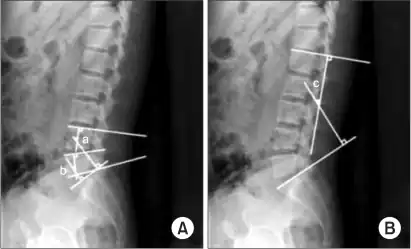

Measurement and diagnosis of lumbar hyperlordosis can be difficult. Obliteration of vertebral end-plate landmarks by interbody fusion may make the traditional measurement of segmental lumbar lordosis more difficult. Because the L4–L5 and L5–S1 levels are most commonly involved in fusion procedures, or arthrodesis, and contribute to normal lumbar lordosis, it is helpful to identify a reproducible and accurate means of measuring segmental lordosis at these levels.[16][17] A visible sign of hyperlordosis is an abnormally large arch of the lower back and the person appears to be puffing out his or her stomach and buttocks.

Precise diagnosis is done by looking at a complete medical history, physical examination and other tests of the patient. X-rays are used to measure the lumbar curvature. On a lateral X-ray, a normal range of the lordotic curvature of between 20° and 60° has been proposed by Stagnara et al., as measured from the inferior endplate of T12 to the inferior endplate of L5.[18] The Scoliosis Research Society has proposed a range of 40° and 60° as measured between the upper endplate of Th12 and the upper endplate of S1.[18] Individual studies, although using other reference points, have found normal ranges up to approximately 85°.[18] It is generally more pronounced in females.[18] It is relatively constant through adolescence and young adulthood, but decreases in the elderly.[18]